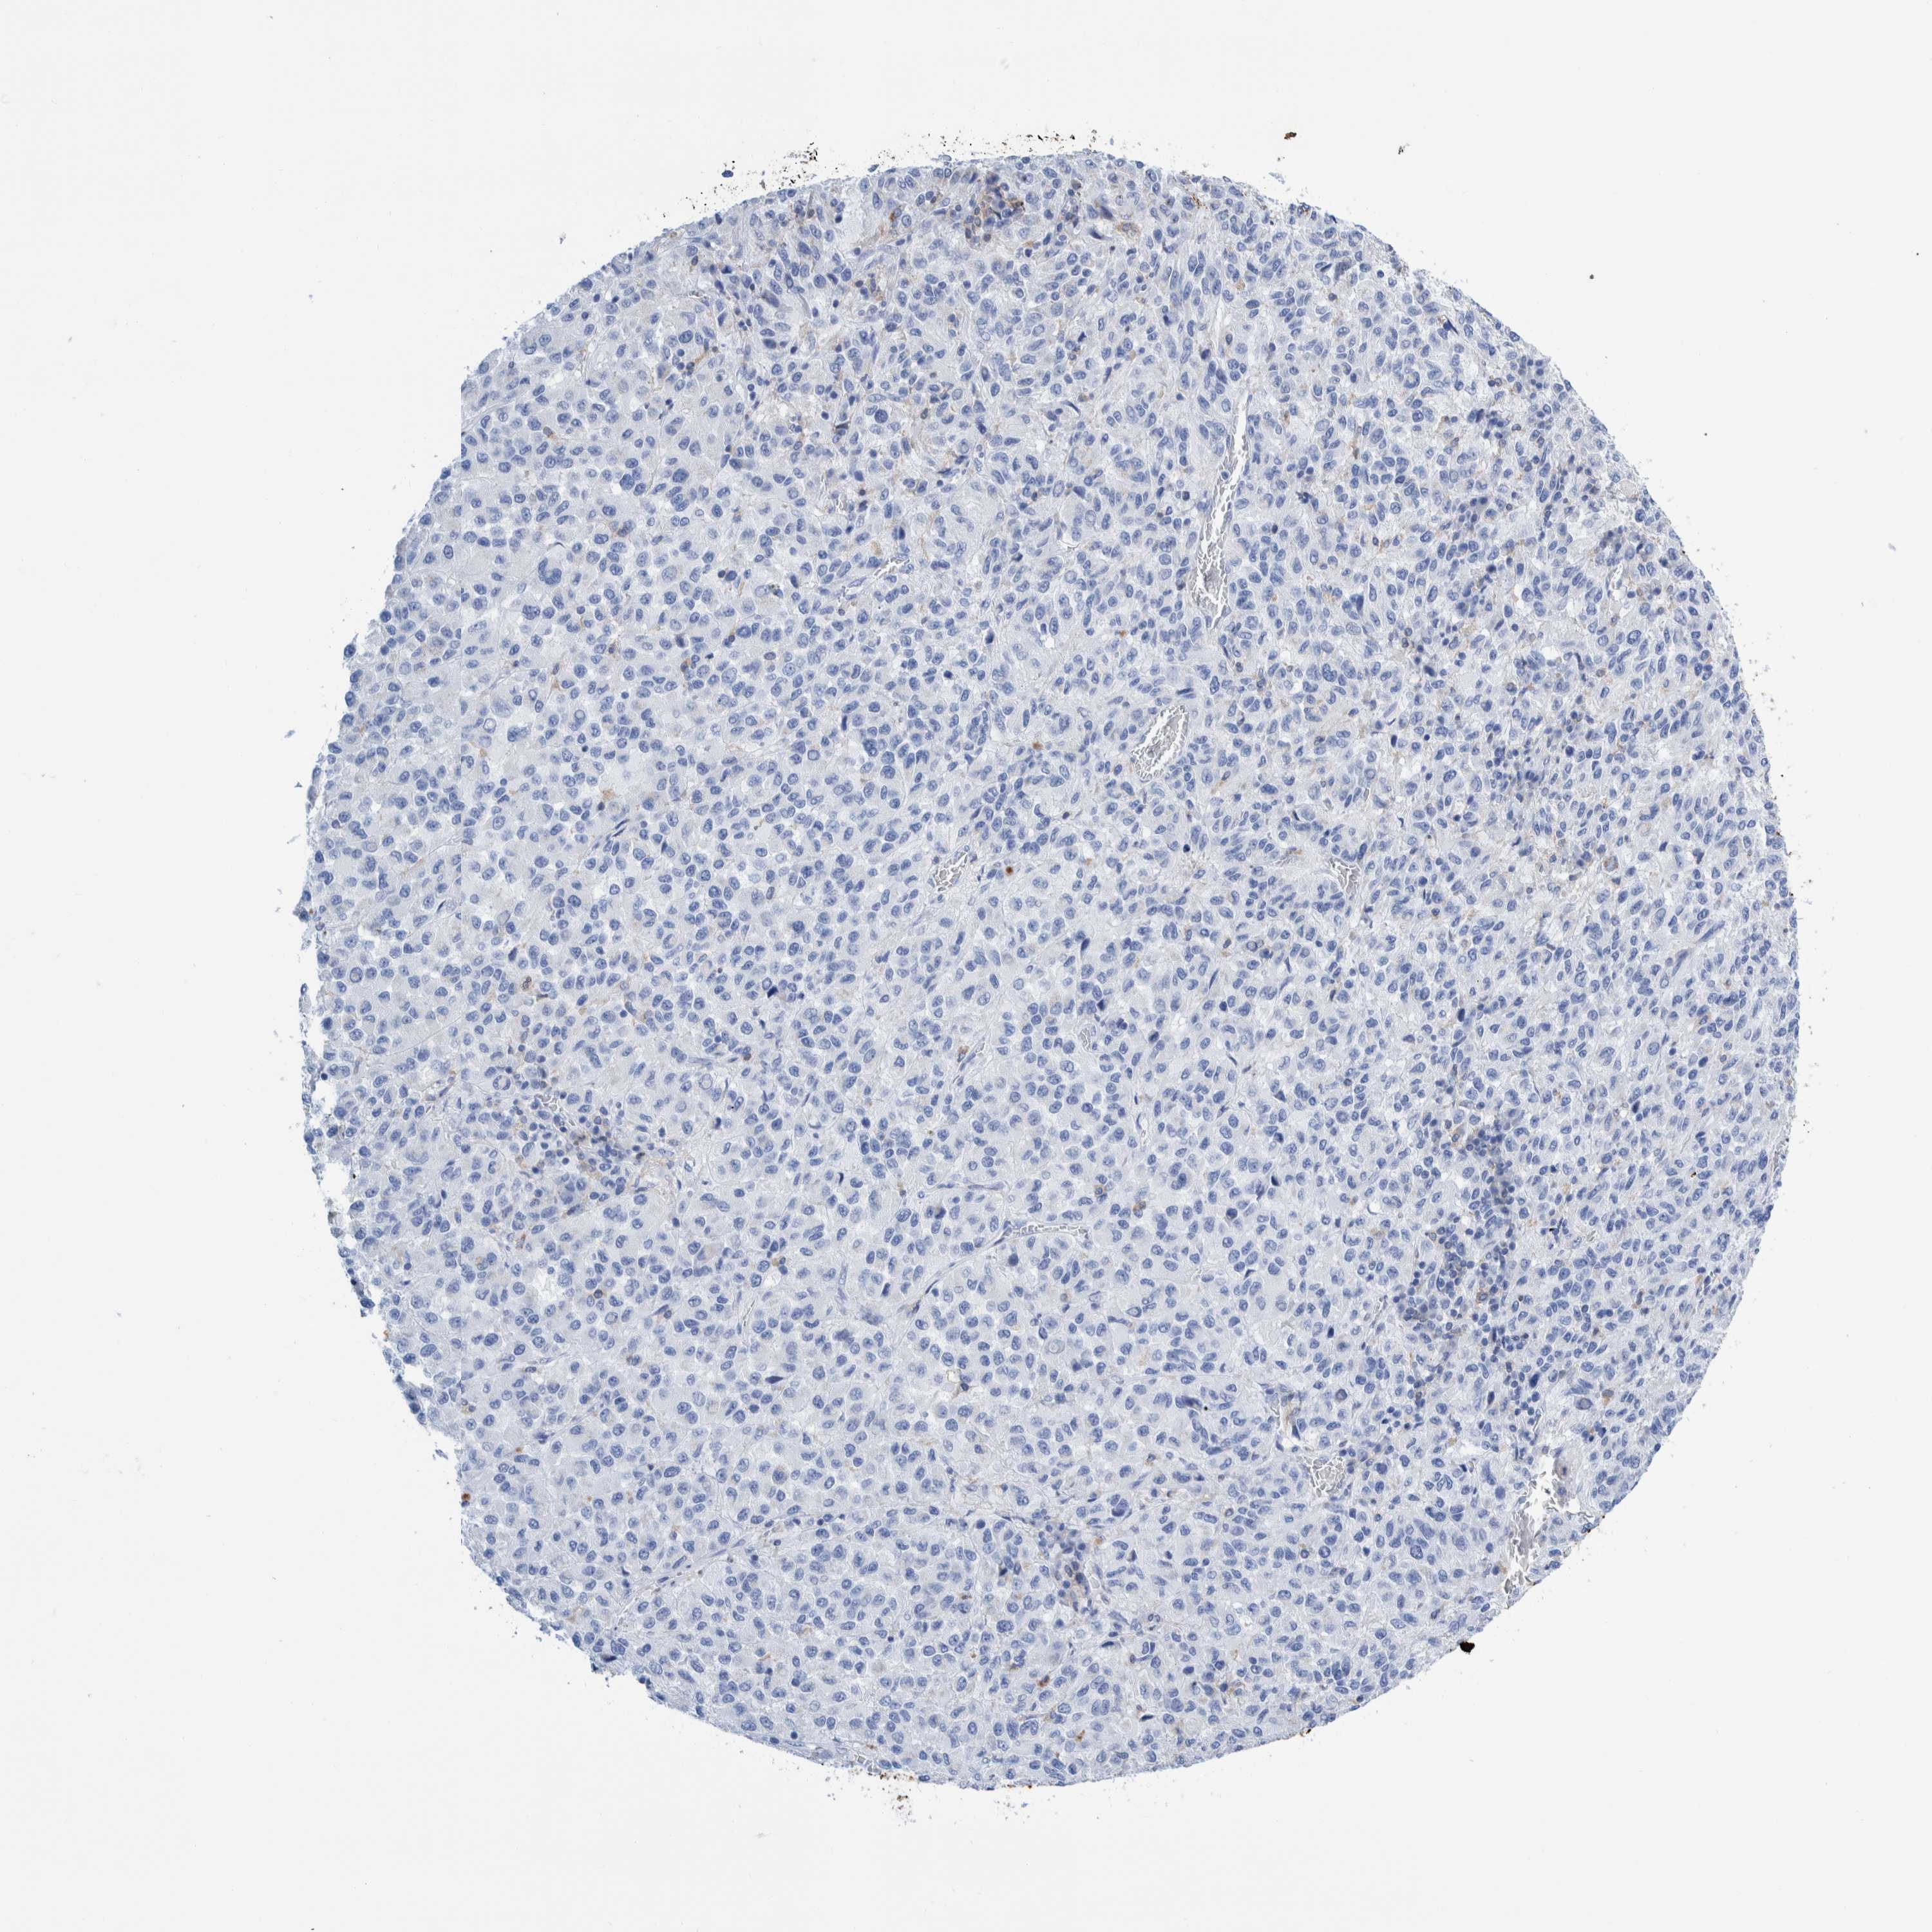

CANCER SKIN CANCER Show tissue menu

SKIN CANCER - Protein expressioni

A mouse-over function shows sample information and annotation data. Click on an image to view it in a full screen mode. Samples can be filtered based on level of antibody staining by selecting one or several of the following categories: high, medium, low and not detected. The assay and annotation is described here.

Each image is clickable and will lead to virtual microscopy that enables deeper exploration of all samples and also displays staining intensity scores, fraction scores and subcellular localization as well as patient and tissue information for each sample.

Antibody HPA000452

Antibody HPA023040

Antibody CAB000134

Squamous cell carcinoma, NOS

Basal cell carcinoma

Squamous cell carcinoma, metastatic, NOS